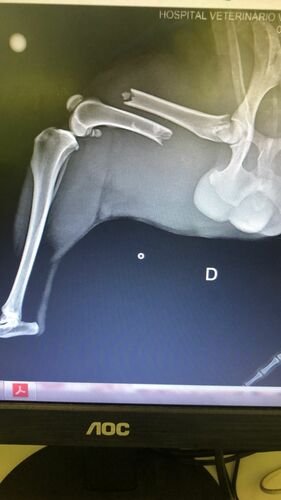

Me chamo Jayani e faço parte do grupo de protetoras voluntárias ao resgate animal! Nosso insta é @miau.viralatasprotegidos! Essa semana resgatamos um cachorrinho atropelado e ele precisou passar por cirurgia e internamento na clínica VitalPet, estamos com gastos altíssimos e torcendo pela sua melhora e que volte a andar! Conto com sua ajuda para custear os gastos 🙏🏻